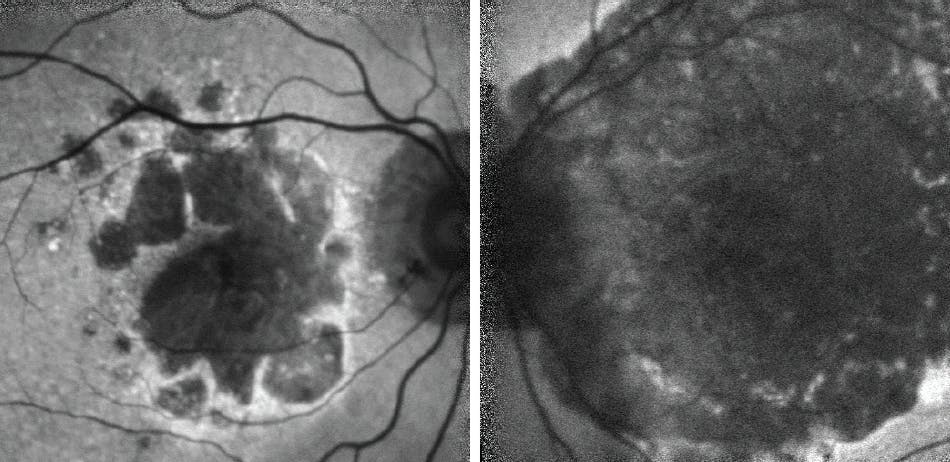

When the patient presented again 2 years after her initial examination, she reported subjective vision loss. FAF imaging revealed significant growth of GA lesions in both eyes (Figure 2). Surprisingly, her BCVA was measured at 20/40 OD and 20/25 OS. Foveal encroachment was present OD and was nearly manifest OS.

Figure 2. Two years after her initial examination, the patient returned complaining of vision loss. GA growth was evident OU, with foveal encroachment observed OD, where her BCVA was measured at 20/40 (A). Despite significant lesion growth OS, her BCVA was unchanged from her previous visit and was measured at 20/25 (B).

OCT imaging at presentation showed evidence of GA OD and exudative changes OU (Figure 6). The patient began anti-VEGF treatment for wet AMD OU. Treatment OS was halted after 10 doses because the patient’s vision did not improve (likely due to the disciform scarring seen on presentation) and at her most recent appointment, her BCVA OS was hand movement. Wet AMD treatment OD has included 52 doses, with BCVA OD at 20/70+1 at the most recent appointment. Over the course of 7 years, the patient subjectively reported declining vision OD, which is likely due to the progression of GA lesions in that eye as shown on FAF (Figure 7) and OCT (Figure 8) at her most recent visit.

Figure 7. FAF imaging 7 years after initial presentation showed significant GA lesion growth OD with foveal involvement, which likely has contributed to declining BCVA despite regular anti-VEGF treatment for wet AMD. Advanced disciform scarring is very pronounced OS.

Figure 8. OCT imaging 7 years after initial presentation shows continued GA progression OD. It was determined that complement inhibition treatment was warranted in this patient.